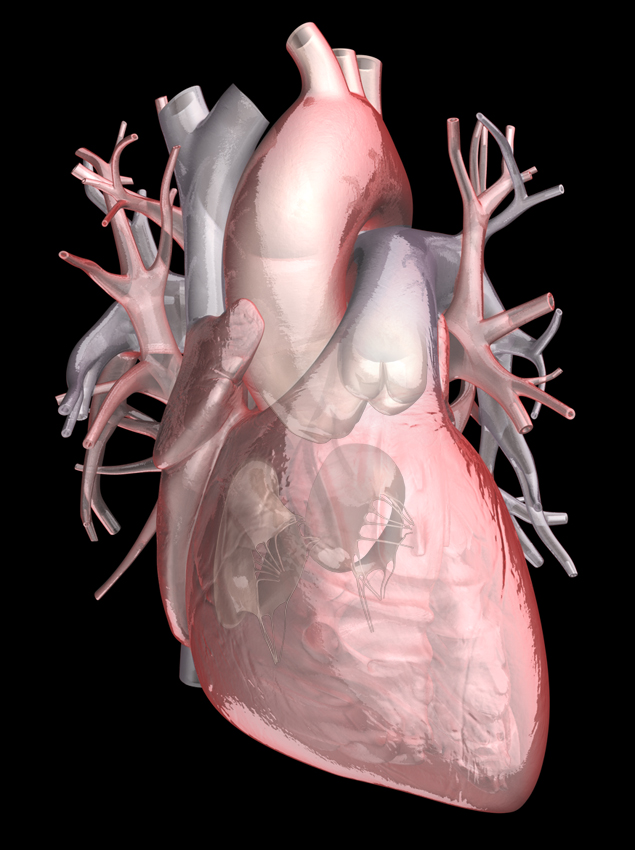

Animated Realistic Human Heart - Medically 3D asset  Zygote::3D Heart Model | Medically Accurate | Human Anatomy

Zygote::3D Heart Model | Medically Accurate | Human Anatomy  Zygote::Solid 3D Human Heart Model

Human Heart Section 3D model | CGTrader  human heart - internal anatomy 3d model

human heart - internal anatomy 3d model  3D Illustration Human Heart 3D Images - Iwish Iwas